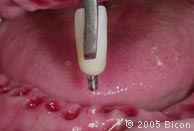

用金色的5.0mm龈沟绞刀去除任何可能会影响一体化基台冠完全就位的骨或软组织。 |

![]() |

21. |

引导杆上带出的多余的骨和软组织。 |